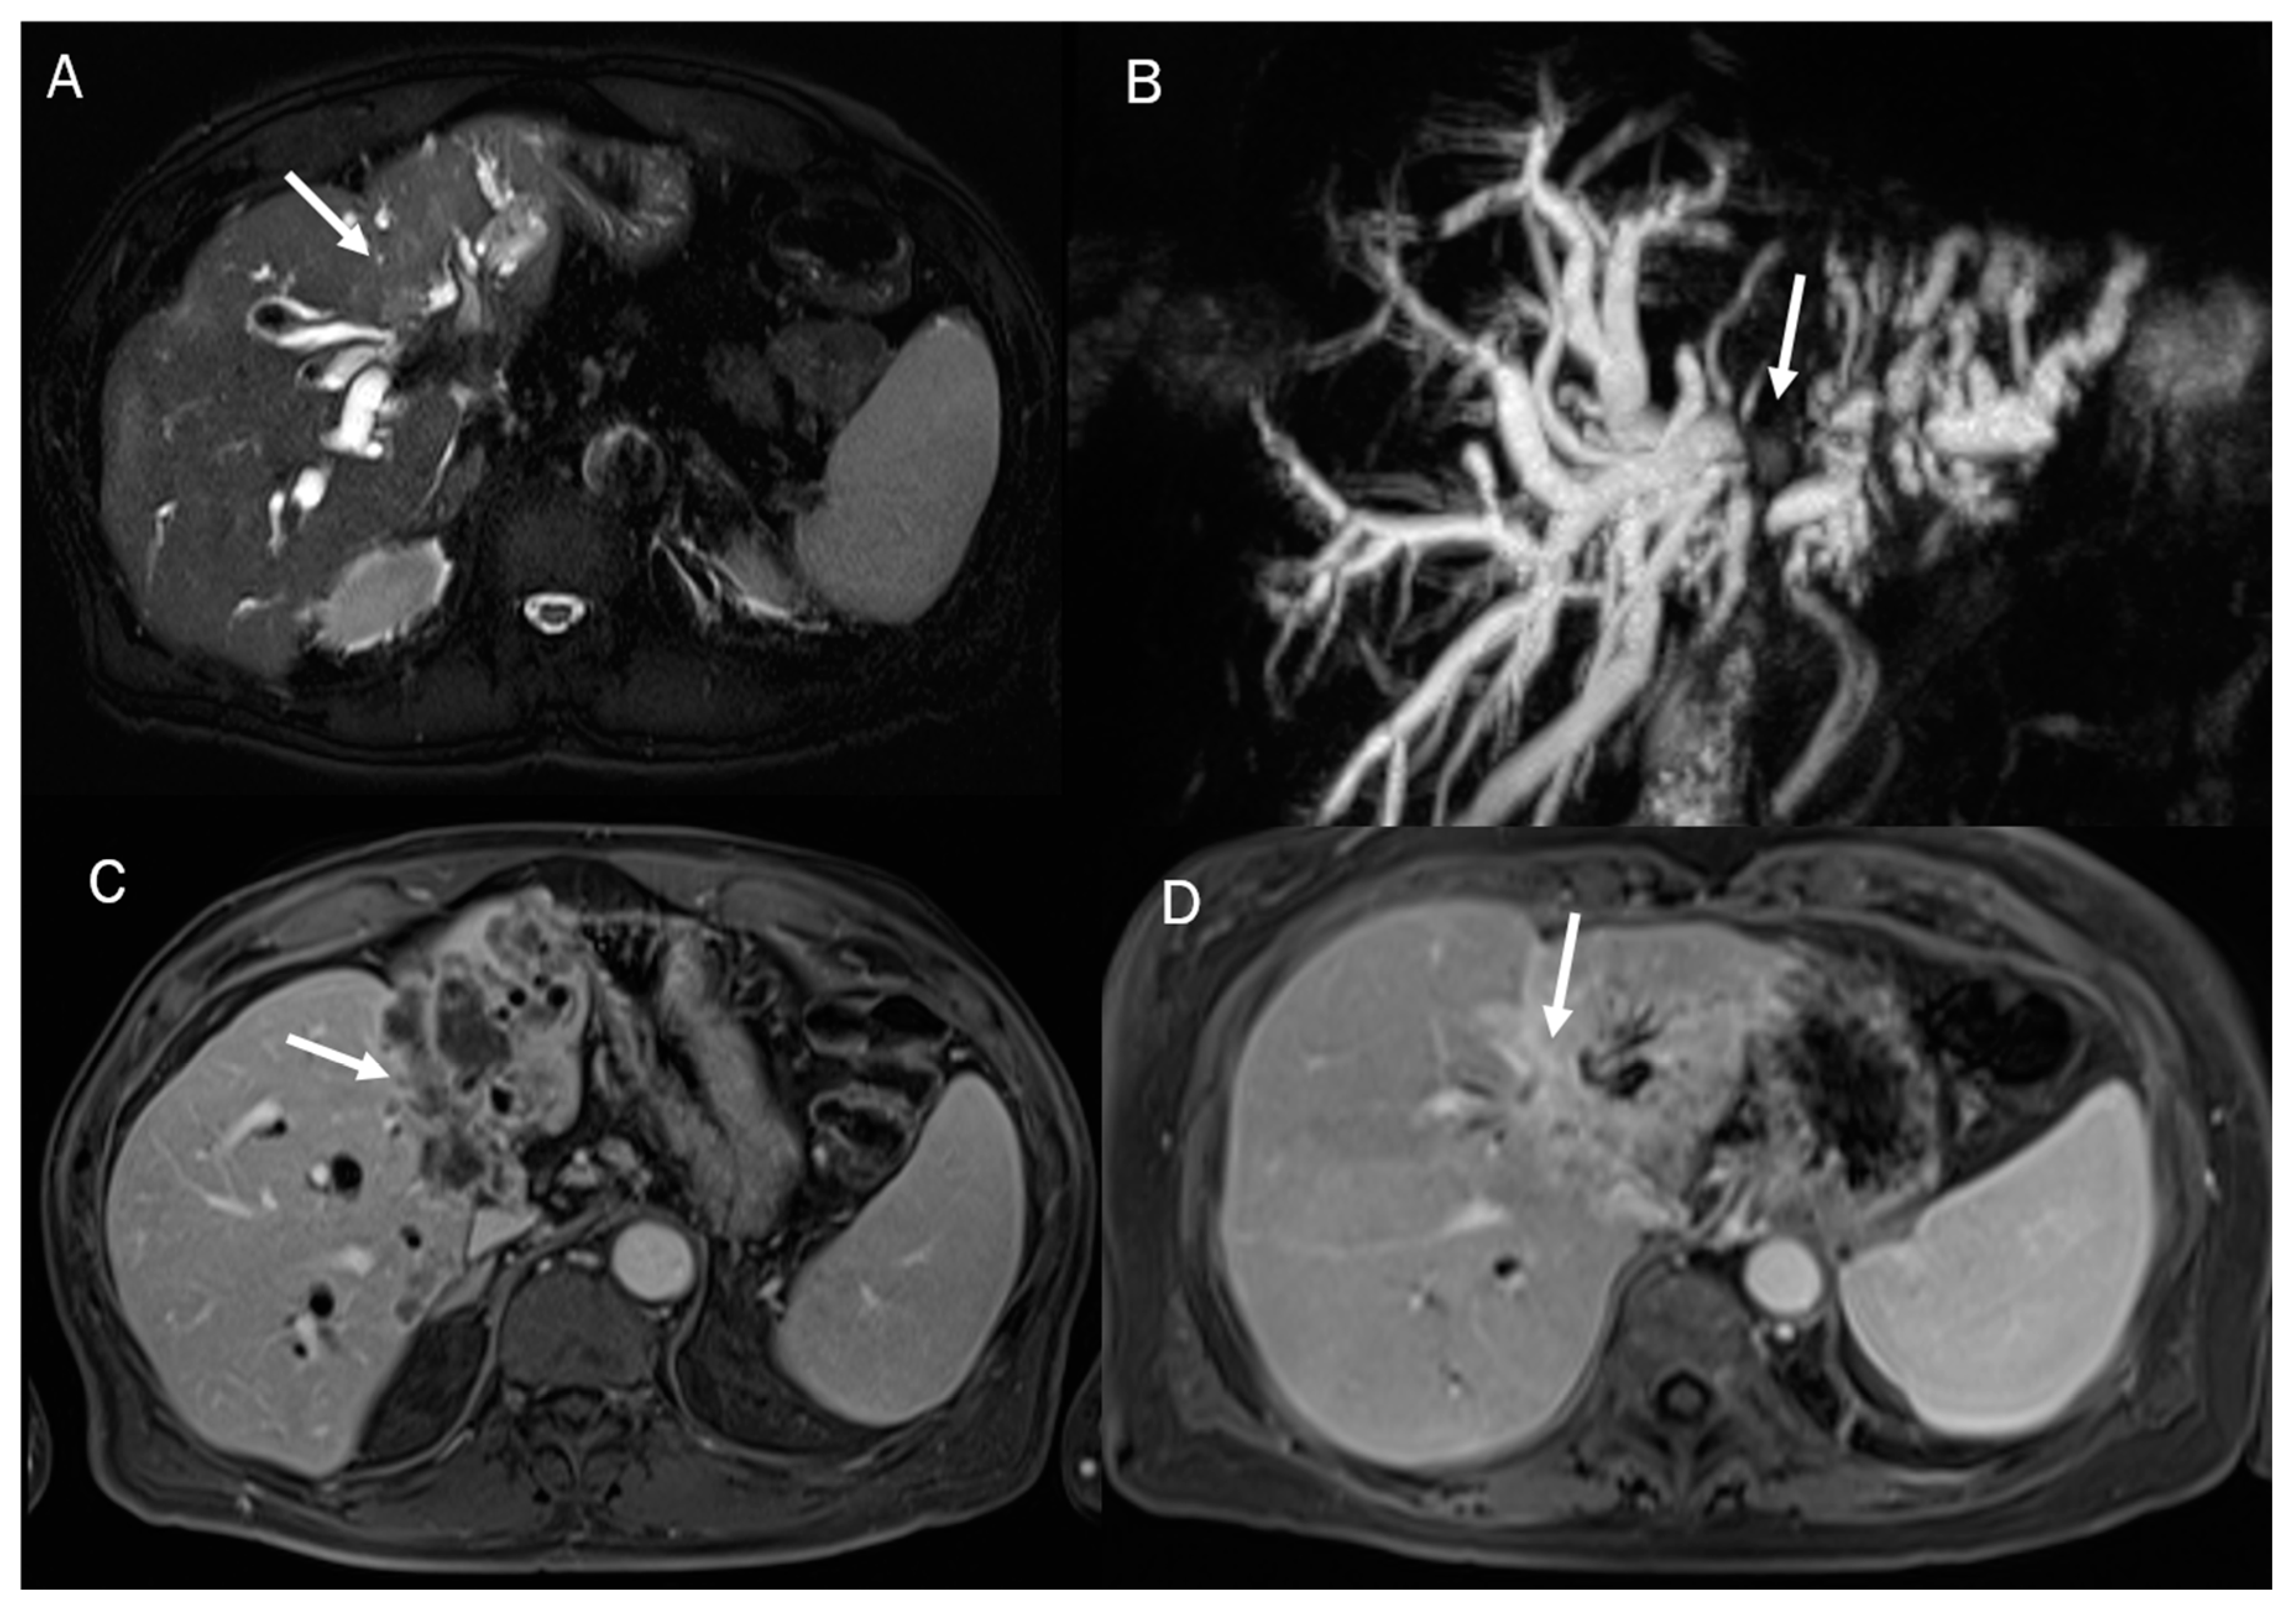

In MRI imaging, ICC presents typical features as capsular retraction adjacent to the tumor. In T1-W sequences, the lesion appears with a targetoid aspect or hypointense signal. While most of the lesions also appear targetoid (Figure 5) in T2 sequences, some can show hyperintense signals. After contrast administration in the arterial phase in ICC, it is possible to identify the peripheral rim hyperenhanced. In the portal phase, the lesion slowly increases its entire enhancement (Figure 5 and Figure 6) [181,182,183,184].

Figure 5.

ICC MRI assessment. The lesion (arrow) shows hypointense signal in T2-W sequence (A) due to fibrotic tissue, with targetoid appearance in DWI (B) and ADC map (C) and progressive contrast enhancement during arterial (D), portal (E), and delay (F) phases of contrast study.

Figure 6.

MRI assessment of periductal-infiltrating CCA. The lesion (arrow) shows hyperintense signal in T2-W (A), causing biliary tree dilatation in cholangiography sequences (B). During arterial phase (C), the lesion causes hyperenhancement of surrounding liver parenchymal, showing a progressive contrast enhancement in portal phase (D).